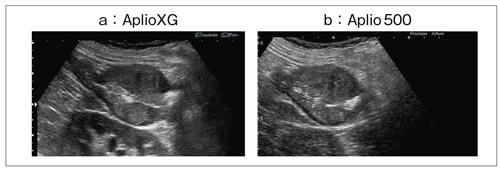

(2)Precision Imaging,ApliPure+

Aplio500では,Precision ImagingとApliPure+がHDBでさらに高画質化された。Precision は,ノイズ成分を低減し,コントラスト分解能や均一性,組織の連続性を高め,ApliPure+は,コンパウンド技術による画像の鮮明化や,スペックルノイズの低減,また,深部感度の向上を可能にする。

図2は,下行結腸がん症例での,いわゆるpseudo kidney signを呈した画像である。Precision Imaging によるAplioXG画像(図2 a)では,画質の視認性は向上するが白さが強調されやや誇張され過ぎた画質となっていたが,Aplio500(図2 b)では白さが抑えられ,辺縁がきれいにつながったイメージに表現され,Precision Imagingの持つ特徴をより生かしたものに改善されている。

図2 Precision ImagingとApliPureを適応した下行結腸がん症例